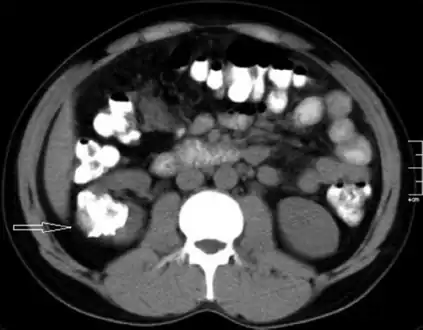

Left flank pain and gross hematuria diagnosed with renal medullary fibroma

Low mag.

High mag.